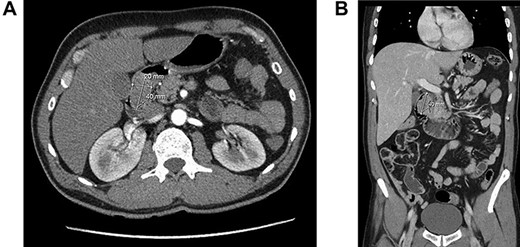

A 57-year-old man was referred because of 4 months history of dyspepsia, 4 kg weight loss and one episode of coffee emesis. Physical examination was unremarkable. Laboratory investigations were within normal limits. Computed tomography (CT) demonstrated a round soft tissue density lesion in the proximal duodenum, measuring 2 × 4 cm (Fig. 1a and b).

Computed tomography of duodenal Brunner’s gland hamartoma. (a) Axial plane. (b) Coronal plane.